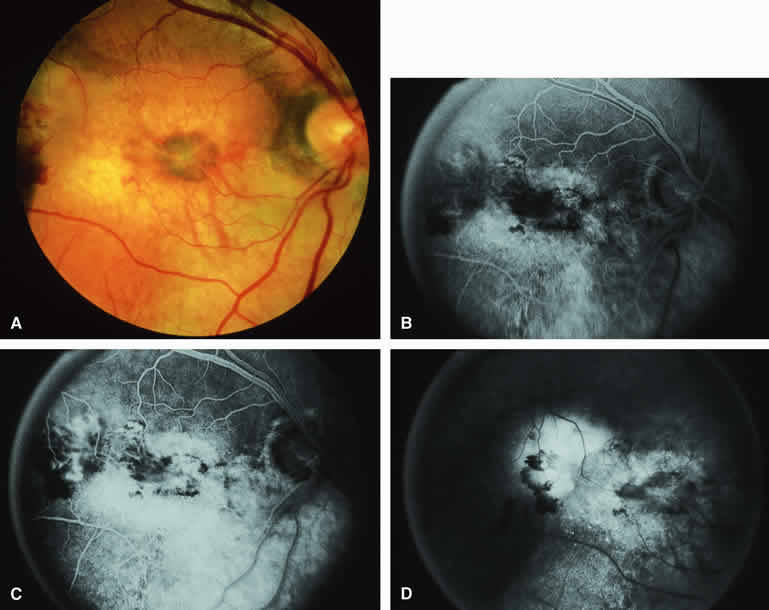

Choroidal Nevus with Drusen and Clumps of RPE Hyperplasia

If a choroidal nevus has drusen and RPE alterations on its surface (see Fig. 4A), fluorescein angiography (Fig. 4B, C, and D) tends to show patchy or stippled window defect hyperfluorescence corresponding to foci of RPE depigmentation, fluorescence blockage by clumps of RPE hyperplasia on the surface of the lesion, and late staining of at least some of the drusen. These features are not usually as evident on ICG angiography as they are on fluorescein angiography.